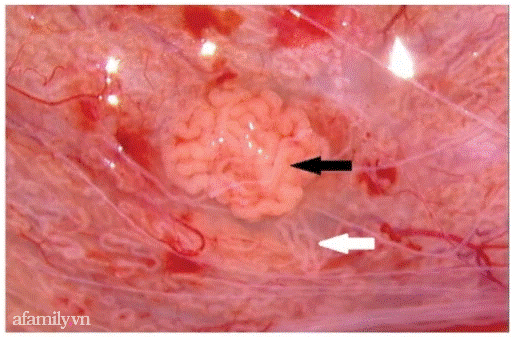

Micro TESE là phẫu thuật vi phẫu can thiệp sâu vào tinh hoàn để tìm những ống sinh tinh có chứa tinh trùng thông qua kính vi phẫu có độ phóng đại lớn. Khi tìm tinh trùng trên những mẫu mô nhỏ, việc lọc tách cũng rất khó khăn, đòi hỏi sự tỉ mỉ. Phẫu thuật Micro TESE đôi khi chỉ có thể tìm được một vài tinh trùng hoặc vài chục con vừa đủ để làm thụ tinh ống nghiệm. Bác sĩ mổ phải có kinh nghiệm "căn" rất chuẩn sao cho tinh trùng lấy ra là vừa đủ, không lấy quá nhiều mô gây tổn thương tinh hoàn.

Bác sĩ thực hiện phẫu thuật vi phẫu tinh hoàn tìm tinh trùng Micro TESE trên bệnh nhân vô tinh

Bác sĩ thực hiện thủ thuật xẻ mô để thu được mẫu mô tinh hoàn, mô sau khi thu nhận được cắt nhỏ hoặc ép nghiền để thu tế bào đơn. Mẫu sẽ được quan sát tìm tinh trùng dưới hệ thống kính hiển vi với độ phóng đại 400 lần. Tinh trùng nếu có sẽ được thu nhận, xử lý và sử dụng trong điều trị thụ tinh trong ống nghiệm. Ảnh: Internet.

Micro TESE là kỹ thuật mổ tinh hoàn và soi dưới kính hiển vi tìm từng tổ chức ống sinh tinh (là một cấu trúc rất nhỏ trong tinh hoàn đảm nhiệm chức năng sản sinh ra tinh trùng) để kiểm tra và tìm tinh trùng. Có thể hình dung đây là phương pháp can thiệp sâu vào tinh hoàn để bác sĩ "bắt" từng con tinh trùng.

2. Bằng kinh nghiệm, trình độ chuyên môn, bác sĩ sẽ chọn những ống sinh tinh tốt nhất trong tinh hoàn thông qua kính vi phẫu có độ phóng đại gấp nhiều lần.

3. Các ống sinh tinh "khỏe mạnh" sẽ được tách nhỏ để soi tìm tinh trùng. Phẫu thuật kết thúc khi tìm thấy đủ tinh trùng đạt điều kiện thụ tinh trong ống nghiệm với trứng của người vợ.